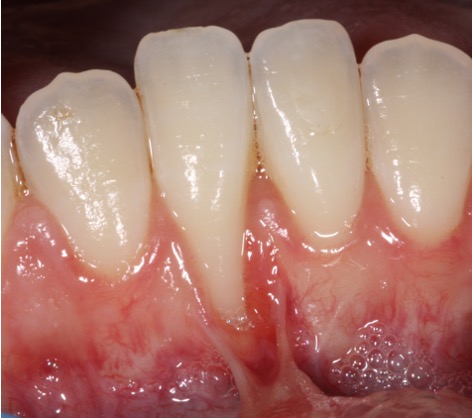

Recession surgery – Free gingival graft

A free gingival graft can cover the recession area and provide “tougher” gum to prevent further recession and make brushing more comfortable. This can also be done around implants. The graft is taken from the roof of the mouth which heals over after a few weeks.